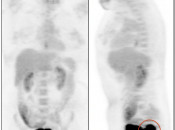

Value of the Sagittal PET Images:

- A careful review of these sagittal images is especially important to catch lesions involving the rectum, uterus and spine that can be easily overlooked with axial imaging alone. [Case 5] [Case 6] [Case 7]

- Case 441: Rectal cancer

uick MIP Coronal: superimposed on bladder

Quick MIP Sagittal: See mass!

Rotating MIP: Great way to see this phenomenon

Axial: 180-202 (not needed?) - Case 375: Cervical cancer

Quick MIP Coronal: superimposed on bladder

Axial: 170-192 (not needed?) - Case 440: Met to spine and cord (hidden behind heart on coronal MIP)